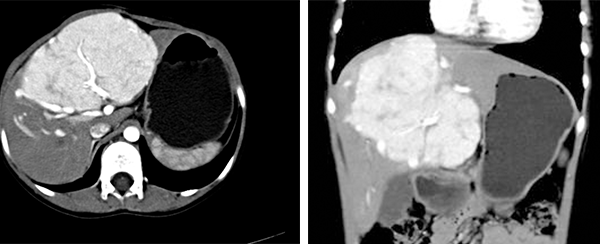

图3:肝右叶肝母细胞瘤的CT 表现 图4:肝右叶肝母细胞瘤的CT表现

图5:肝左叶肝母细胞瘤合并肝内转移

(1)CT表现

1)平扫:可见肝实性肿块,多由数个结节聚合成大块状,其边缘为高或等密度,中心呈低密度或高低不等密度。

2)增强扫描:在动脉期增强可见多个结节状增强染色征象,门静脉期肿瘤呈低密度,中心有不规则更低密度区域,为肿瘤坏死所致。有的肿瘤内含类似骨组织成分,CT 可显示钙化灶。CT平扫示右肝可见巨块状低密度占位性病变,边缘比较光滑,密度不均,内部可见不规则更低密度区域,其内斑点状钙化。增强示肿瘤可见增强,门静脉期肿瘤呈低密度,中心坏死无增强,肝内胆管扩张。